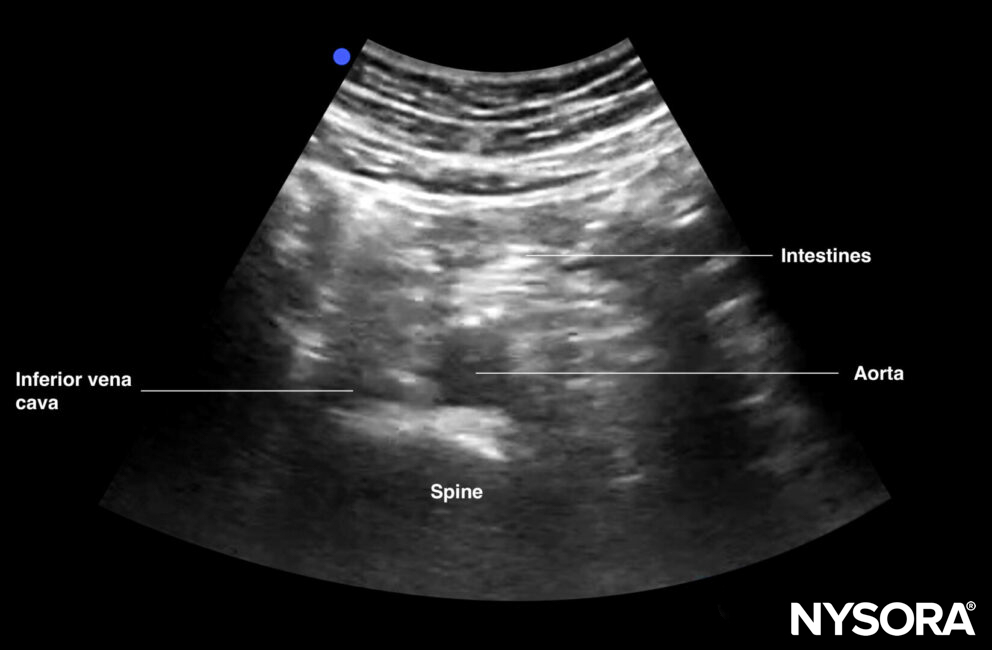

Distal aorta

Transverse view of the distal aorta: transition of the aorta into the bifurcation of the iliac arteries, iliac veins, spine, and intestines.

Transverse view of the distal aorta.

Notes

- The umbilicus corresponds to L4. This is the point where the aorta bifurcates into the iliac arteries.

- The umbilicus may be air-filled, leading to scattering artifacts. Use plenty of gel to fill the umbilicus and eliminate air for better images. Scanning distally or proximally toward the belly button while tilting the transducer may also help eliminate artifacts and visualize the aorta.